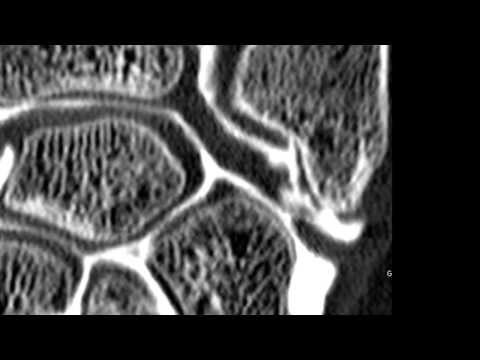

La pseudarthrose est une fracture qui n’a pas consolidée. Elle peut intéresser tous les segments osseux (par exemple l’humérus, le tibia, le scaphoïde au poignet

Chirurgie du poignet sous arthroscopie pour une fracture du scaphoïde, Toulouse :

Chirurgie du poignet sous arthroscopie pour une pseudarthrose du scaphoïde, Toulouse :